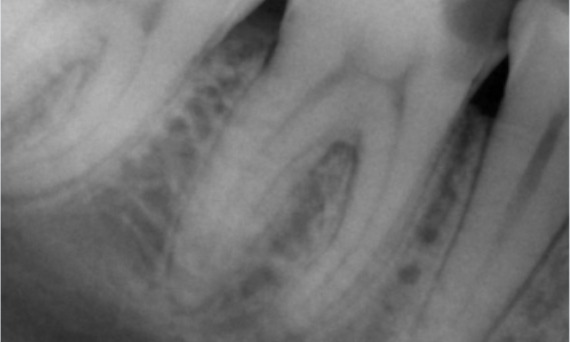

Przed: Podczas badania stwierdzono zmianę próchnicową związaną z dolnym prawym pierwszym trzonowcem. Badanie radiologiczne wykazało bliskość zmiany do rogu miazgi. Łącząc to z główną skargą pacjenta, postawiono ostateczną diagnozę przewlekłego nieodwracalnego zapalenia miazgi.

Po: Dostęp do ubytku został wykonany tak zachowawczo, jak to tylko możliwe. System TruNatomy został wybrany ze względu na młody wiek pacjenta. Musieliśmy zachować zębinę w jak największym stopniu, aby zwiększyć zdolność zęba do pokonywania obciążeń okluzyjnych i zwiększyć trwałość ostatecznej odbudowy.